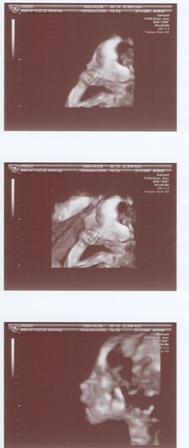

22 hetes UH